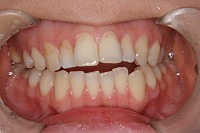

正面

25歳6ヵ月